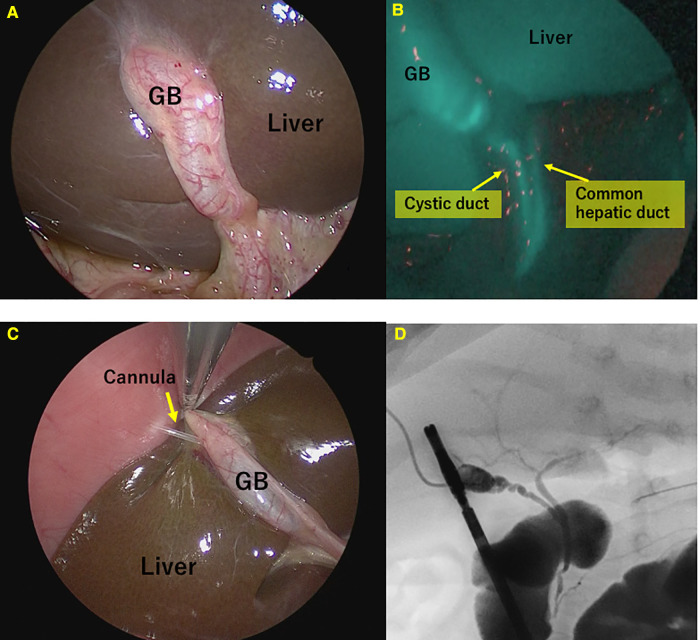

Single-port surgery, conducted only through the umbilical opening, was performed until the BA was definitively diagnosed. A multichannel port was inserted through the umbilical wound, one 5-mm camera port, and two 3-mm ports for the surgeon’s right and left forceps. First, we confirmed the gross liver findings (Figure 1A). An intraoperative liver biopsy was first performed for intraoperative pathological diagnosis, and after hemostasis of the liver tissue, ICG fluorescence cholangiography was performed to observe the gallbladder and bile ducts(Figure 1B). The camera was placed in close proximity to the extrahepatic bile duct or slightly further away to observe the entire image, changing the distance several times so that the gallbladder to the duodenum was in the field of view at 1x. Although ICG fluorescence cholangiography showed that the bile ducts could be observed and BA could be ruled out, conventional cholangiography was still performed. The cannula was inserted via a gallbladder puncture either percutaneously or after being pulled out in the abdominal cavity(Figure 1C). Subsequently, the contrast agent was injected under radiographic guidance to confirm bile flow (Figure 1D).